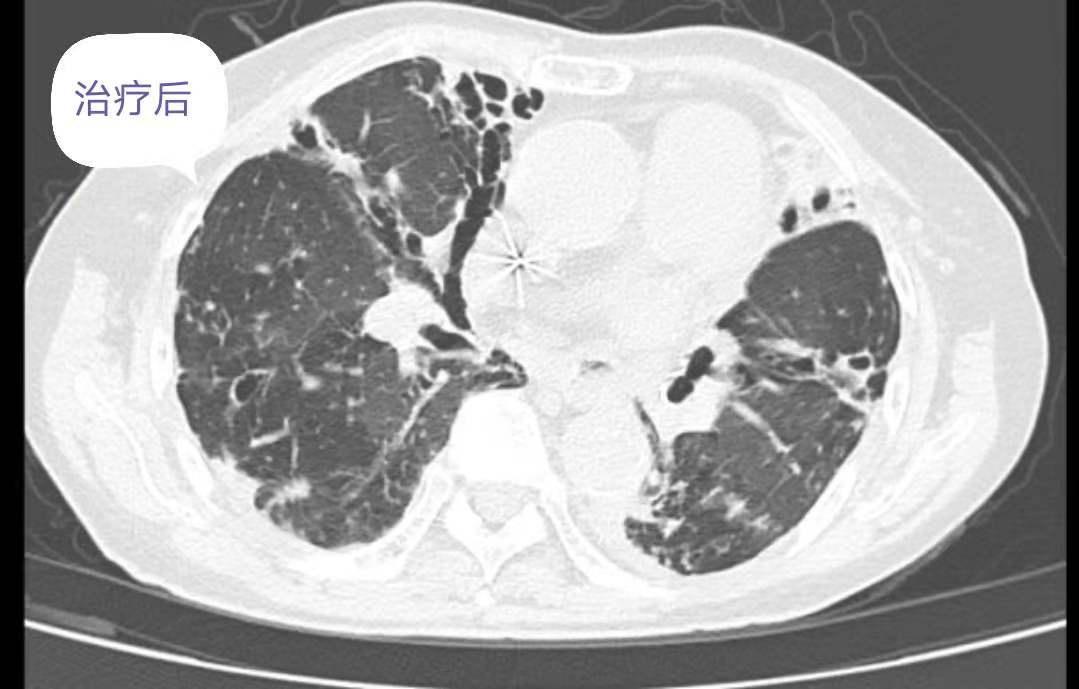

2019.08.16--2019.09.01 阿莫西林钠克拉维酸钾 1.2g q8h ivgtt,克拉霉素 0.5g qd po,左氧氟沙星0.5g qd po。治疗近2月后咳嗽、咳痰、气促等症状明显改善。查体:脉搏74次/分,呼吸18次/分,血压131/70mmHg。双肺呼吸音清,未闻及干湿啰音,心律74次/分,律齐。腹软,无压痛,无反跳痛及肌紧张,肠鸣音4次/分。

复查胸部CT:对比前片提示双肺感染灶减前吸收,肺气肿、支气管扩张,肺底少许纤维性病灶。患者病情改善后办理出院,随访期间未诉特殊不是。